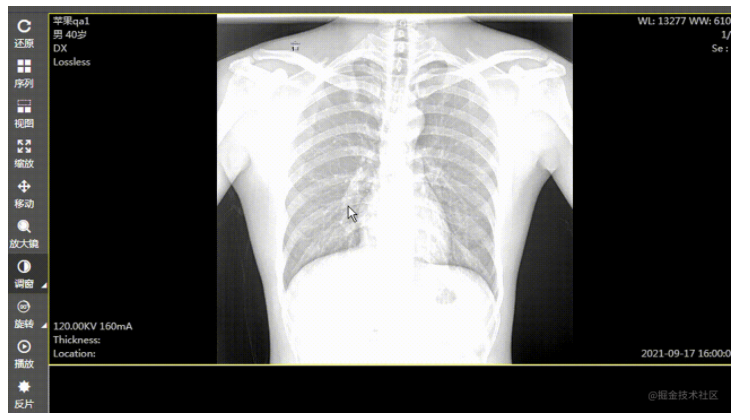

在 web 版阅片器(图像显示工具)的开发工程中发现,在对 dr、dx 这种大图(图像普遍是 2000px 左右宽高的图像,每个像素大小是 16 位或者 32 位的)进行调窗时,浏览器直接卡死,图像显示变化有很大延迟。后来查阅资料,使用 gpujs 来实现调窗时图像的处理,结果:调窗时图像显示变化变得比较线性,性能估计提升 5/6 倍,能满足业务需求。当然,图像的一些高级处理,都是可以用 gpujs 来实现,调窗只是一个点。

使用后效果: